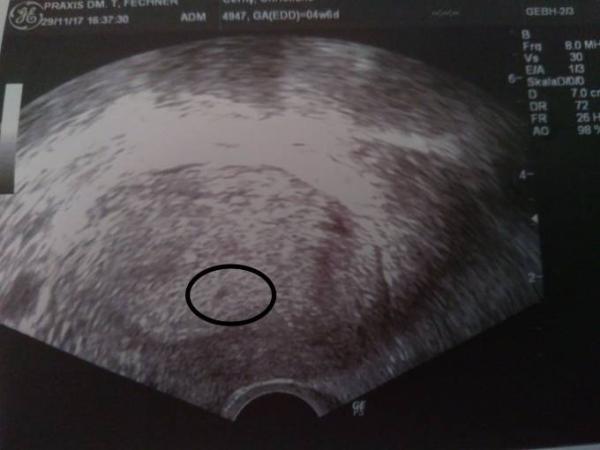

Huhu ihr lieben ... Heute war unser erster Frauenarzt Termin alles gut bin 5 Woche et ist der 2.8.18 freuen uns sehr auf unseren kleinen Klumpen . Hab auch nicht wie andere Damen mit Verstopfung zu kämpfen im Gegenteil hab etwas Durchfall . Werd dies wenn ich am 11.12 wieder hin muss Mal ansprechen oder hat das noch jemand von euch und es ist alles io? Liebe Grüße nane29

Bild zu 1 Frauenarzt Termin - Forum für Juli - Mamis